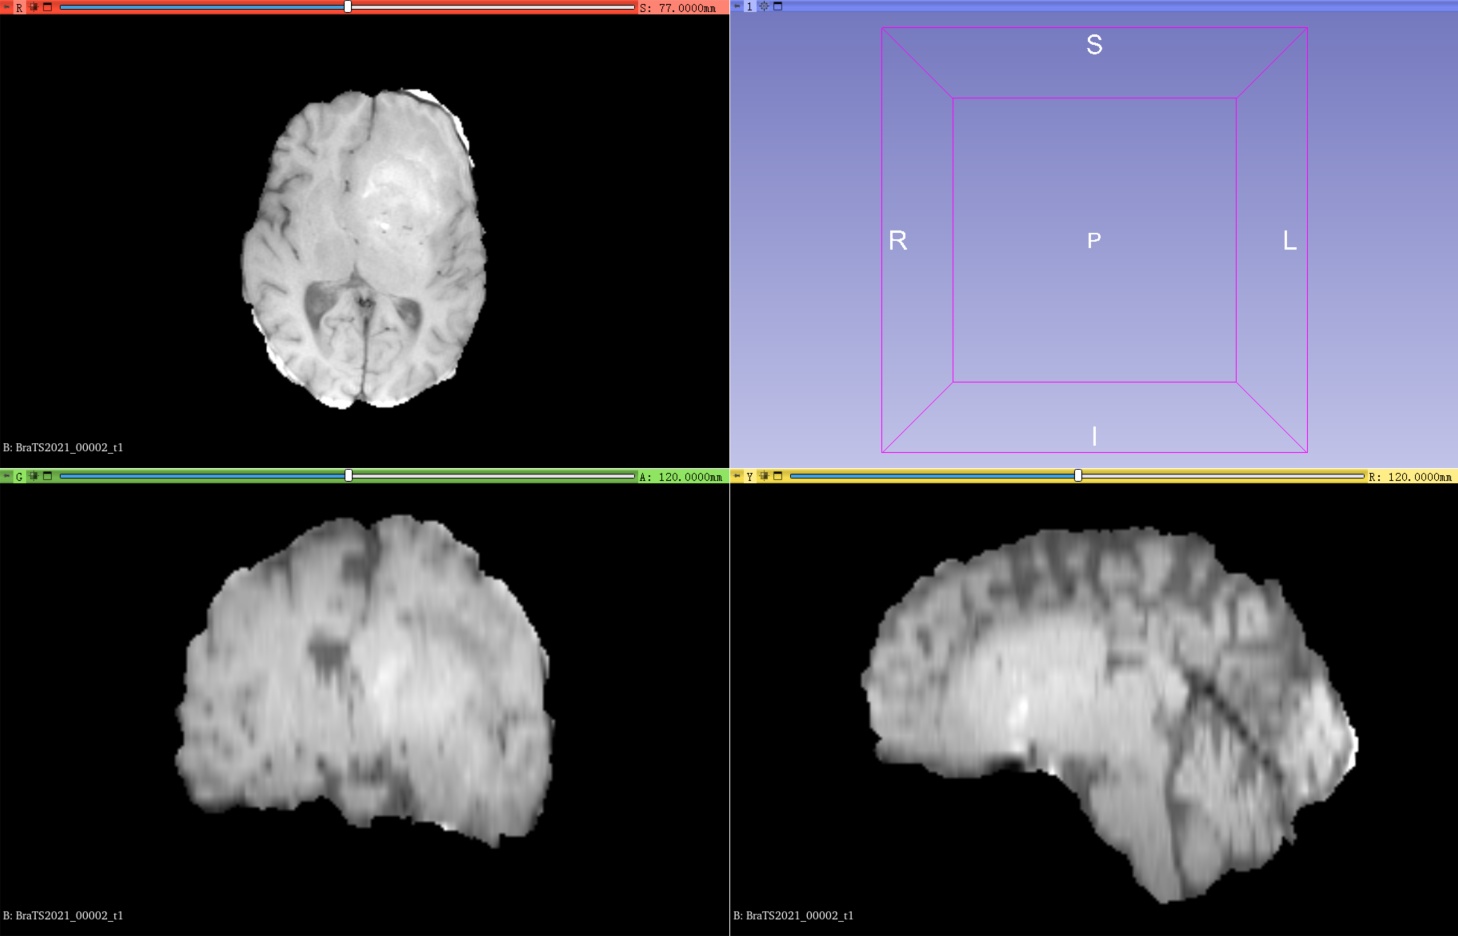

训练集其中一例MRI扫描(包含4个模态的3D图像以及1个共享标签)

1、在训练集中包含1251例核磁共振成像扫描,每例扫描包含4种模态的3D图像以及1个共享标签,其中4种模态分别是t1、t1ce、t2、flair:

T1加权成像(T1-weighted imaging, T1 ):这种成像方式通过对人体进行磁共振成像,使用对T1信号敏感的成像方法,呈现出人体组织的强度。T1序列主要用于显示解剖结构。

BraTS2021_00002_t1.nii.gz |

4、可视化使用3D Slicer查看图像和标签,可以直观的了解自己要用的数据集。左上角代表在Axial(轴向)视角下,可以查看由上到下的脑部二维切片;左下角代表在Coronal(冠状)视角下,可以查看由前到后的脑部二维切片;右下角代表在Sagittal(矢状)视角下,可以查看由左到右的脑部二维切片。